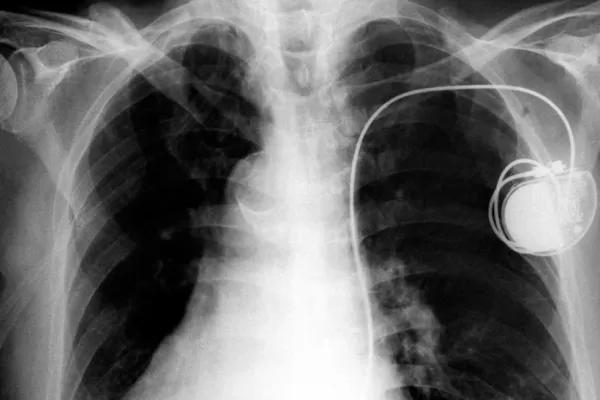

El wifi es un salvavidas de los pacientes con marcapasos

La telemedicina permite a los médicos hacer un seguimiento remoto desde cualquier sitio.